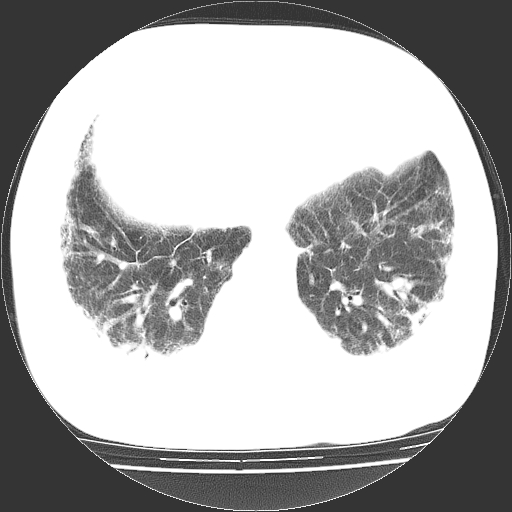

男,68岁,咳嗽、胸闷、发烧三天,查体:双肺散在湿罗音。

依据:1、两肺广泛条索状、网格状、蜂窝状改变。

双肺多发条索状、网格状及小灶状密度增高影。考虑慢支合并感染.间质纤维化,双侧少量胸腔积液

两肺广泛条索状、网格状、蜂窝状改变。肺间质纤维化,肺心病,双侧胸腔积液